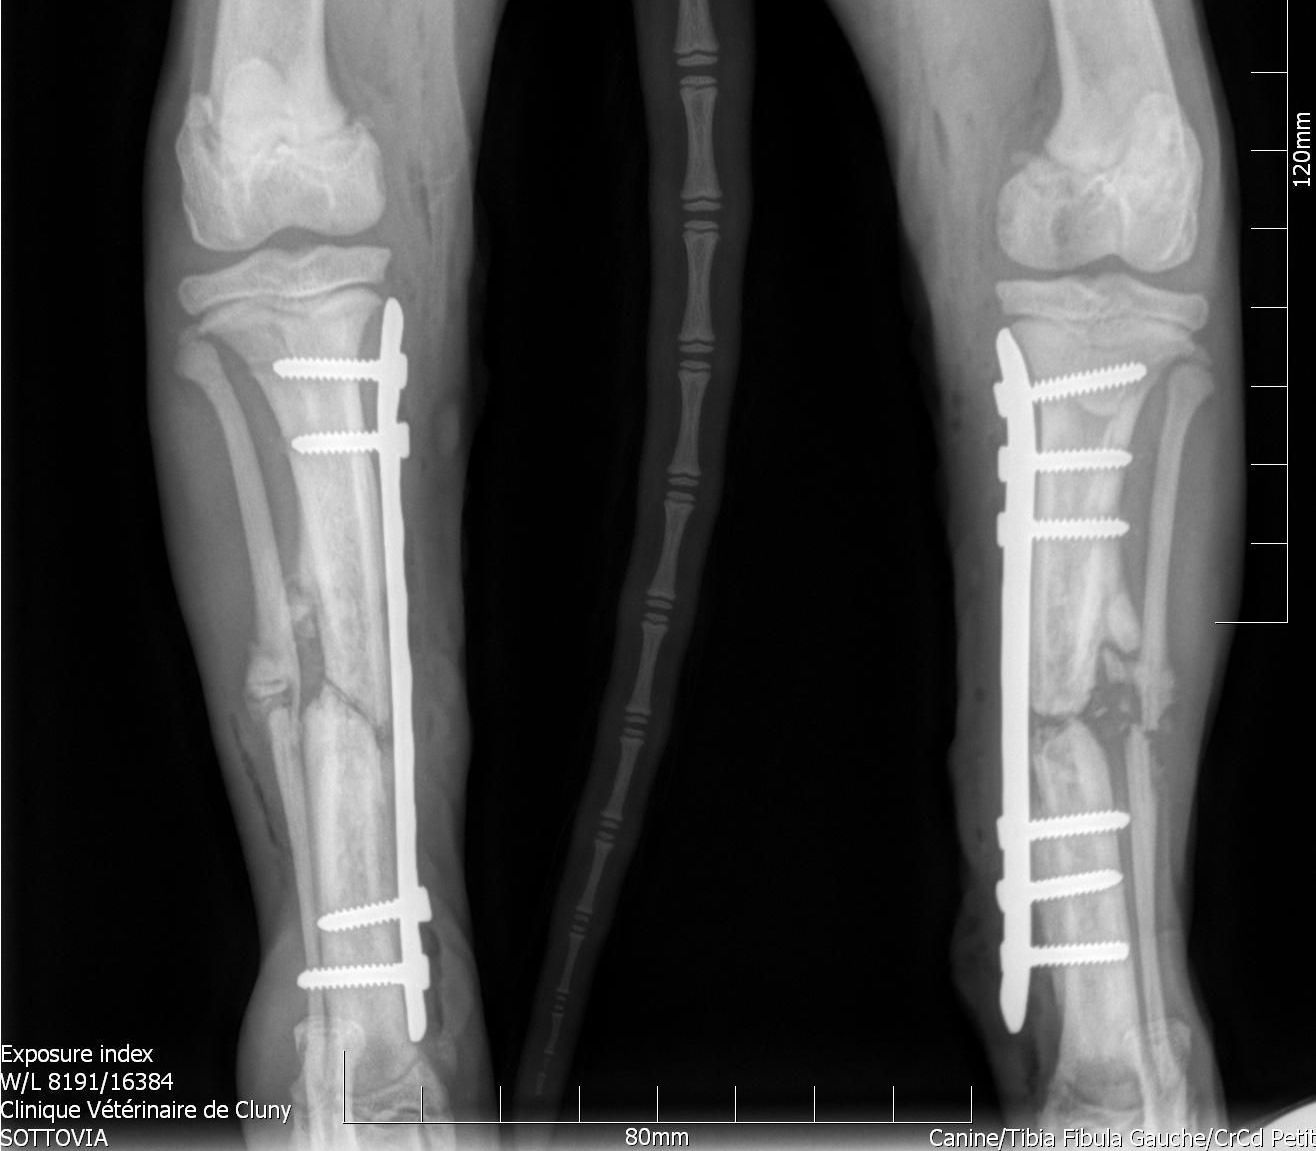

Radiographie

Technique d'imagerie médicale utilisant les rayons X, la radiographie est une des méthodes utilisées pour visualiser les structures internes des animaux.

Elle permet notamment de constater des problèmes comme les fractures, luxations, ainsi que certaines anomalies articulaire.

Selon l'atteinte du patient et les besoins du vétérinaire, les radiographies peuvent être réaliser sur un animal vigil (c'est le cas de la majorité des radios, et ne demande que quelques minutes) ou sur un animal anesthésié (notamment lors de radiographies orthopédique, réalisées par le Dr De Gryse, qui demande plus de temps et un positionnement particulier de l'animal).